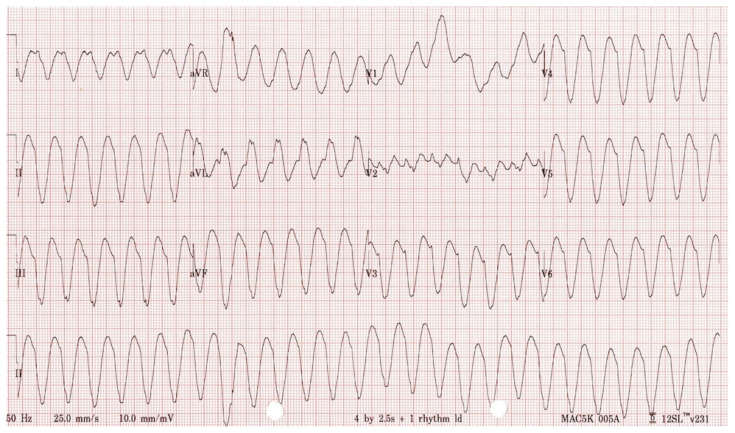

Abstract Image